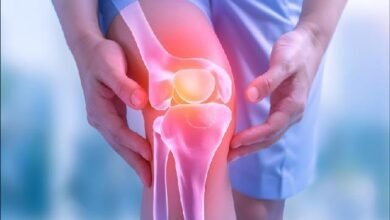

शरीर का सारा Calcium चूस लेंगी, अंदर से खोखली हो जाएगी हड्डियां

डेस्कः आप रोज़ाना कैल्शियम से भरपूर चीज़ें खाती हैं, फिर भी आपकी हड्डियां कमज़ोर हो रही हैं? क्योंकि इसके पीछे एक…